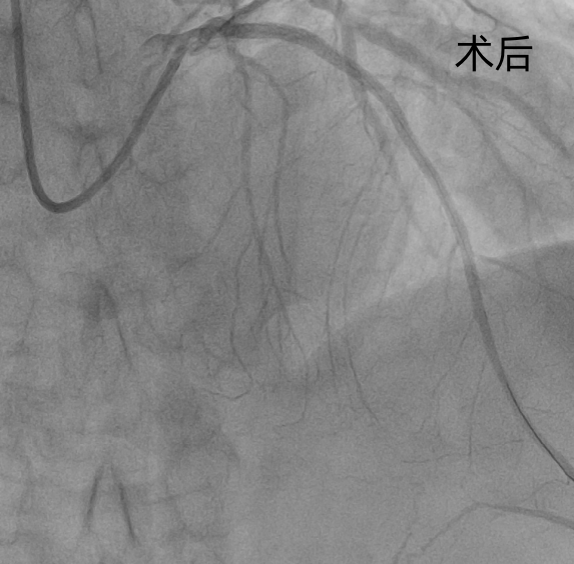

钟先生抵达医院后,直接送入导管室,冠脉造影清晰显示:前降支(LAD)近端完全闭塞,远端血流中断,心肌正处于“断供”坏死的危急状态。

心血管科团队当机立断,迅速实施PCI术,精准植入3枚支架,闭塞血管瞬间恢复通畅。从患者入院到血管成功开通,全程仅用46分钟,远优于国际指南60分钟的标准。